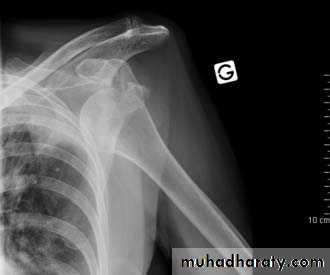

An anterior dislocation is usually caused by excessive extension and lateral rotation of the humerus. The humeral head is forced anteriorly and inferiorly – into the weakest part of the joint capsule. Tearing of the joint capsule is associated with an increased risk of future dislocations.The axillary nerve runs in close proximity to the shoulder joint, and can be damaged in the dislocation. Injury to the axillary nerve causes paralysis of the deltoid, and loss of sensation over regimental badge area. A dislocation can also stretch the radial nerve, as it is tightly bound in the radial groove.

Fig 1.4 – Anterior dislocation of the shoulder joint.